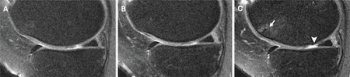

Two years after intraarticular knee injections for knee osteoarthritis (OA), study participants who had corticosteroid knee injections had greater OA progression than control patients while the use of hyaluronic acid injections was associated with less OA progression.